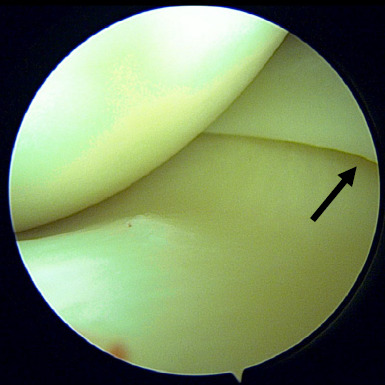

This report presents the case of an 18-year-old female student with a low BMI, who was otherwise healthy. She presented with chronic anterior right knee pain persisting for 1 year. The pain began spontaneously and gradually increased in severity, especially during long distance walking and standing for more than 15 minutes. The symptoms did not subside with medication and physiotherapy. All biochemical and radiological investigations to rule out other related possible aetiologies were unremarkable. The patient eventually underwent an arthroscopic knee surgery, during which the intraoperative findings revealed the Hoffa fat pad over the anteromedial knee joint. This was debrided and after surgery, she was symptom free and had resumed her normal activities.

Abstract Image